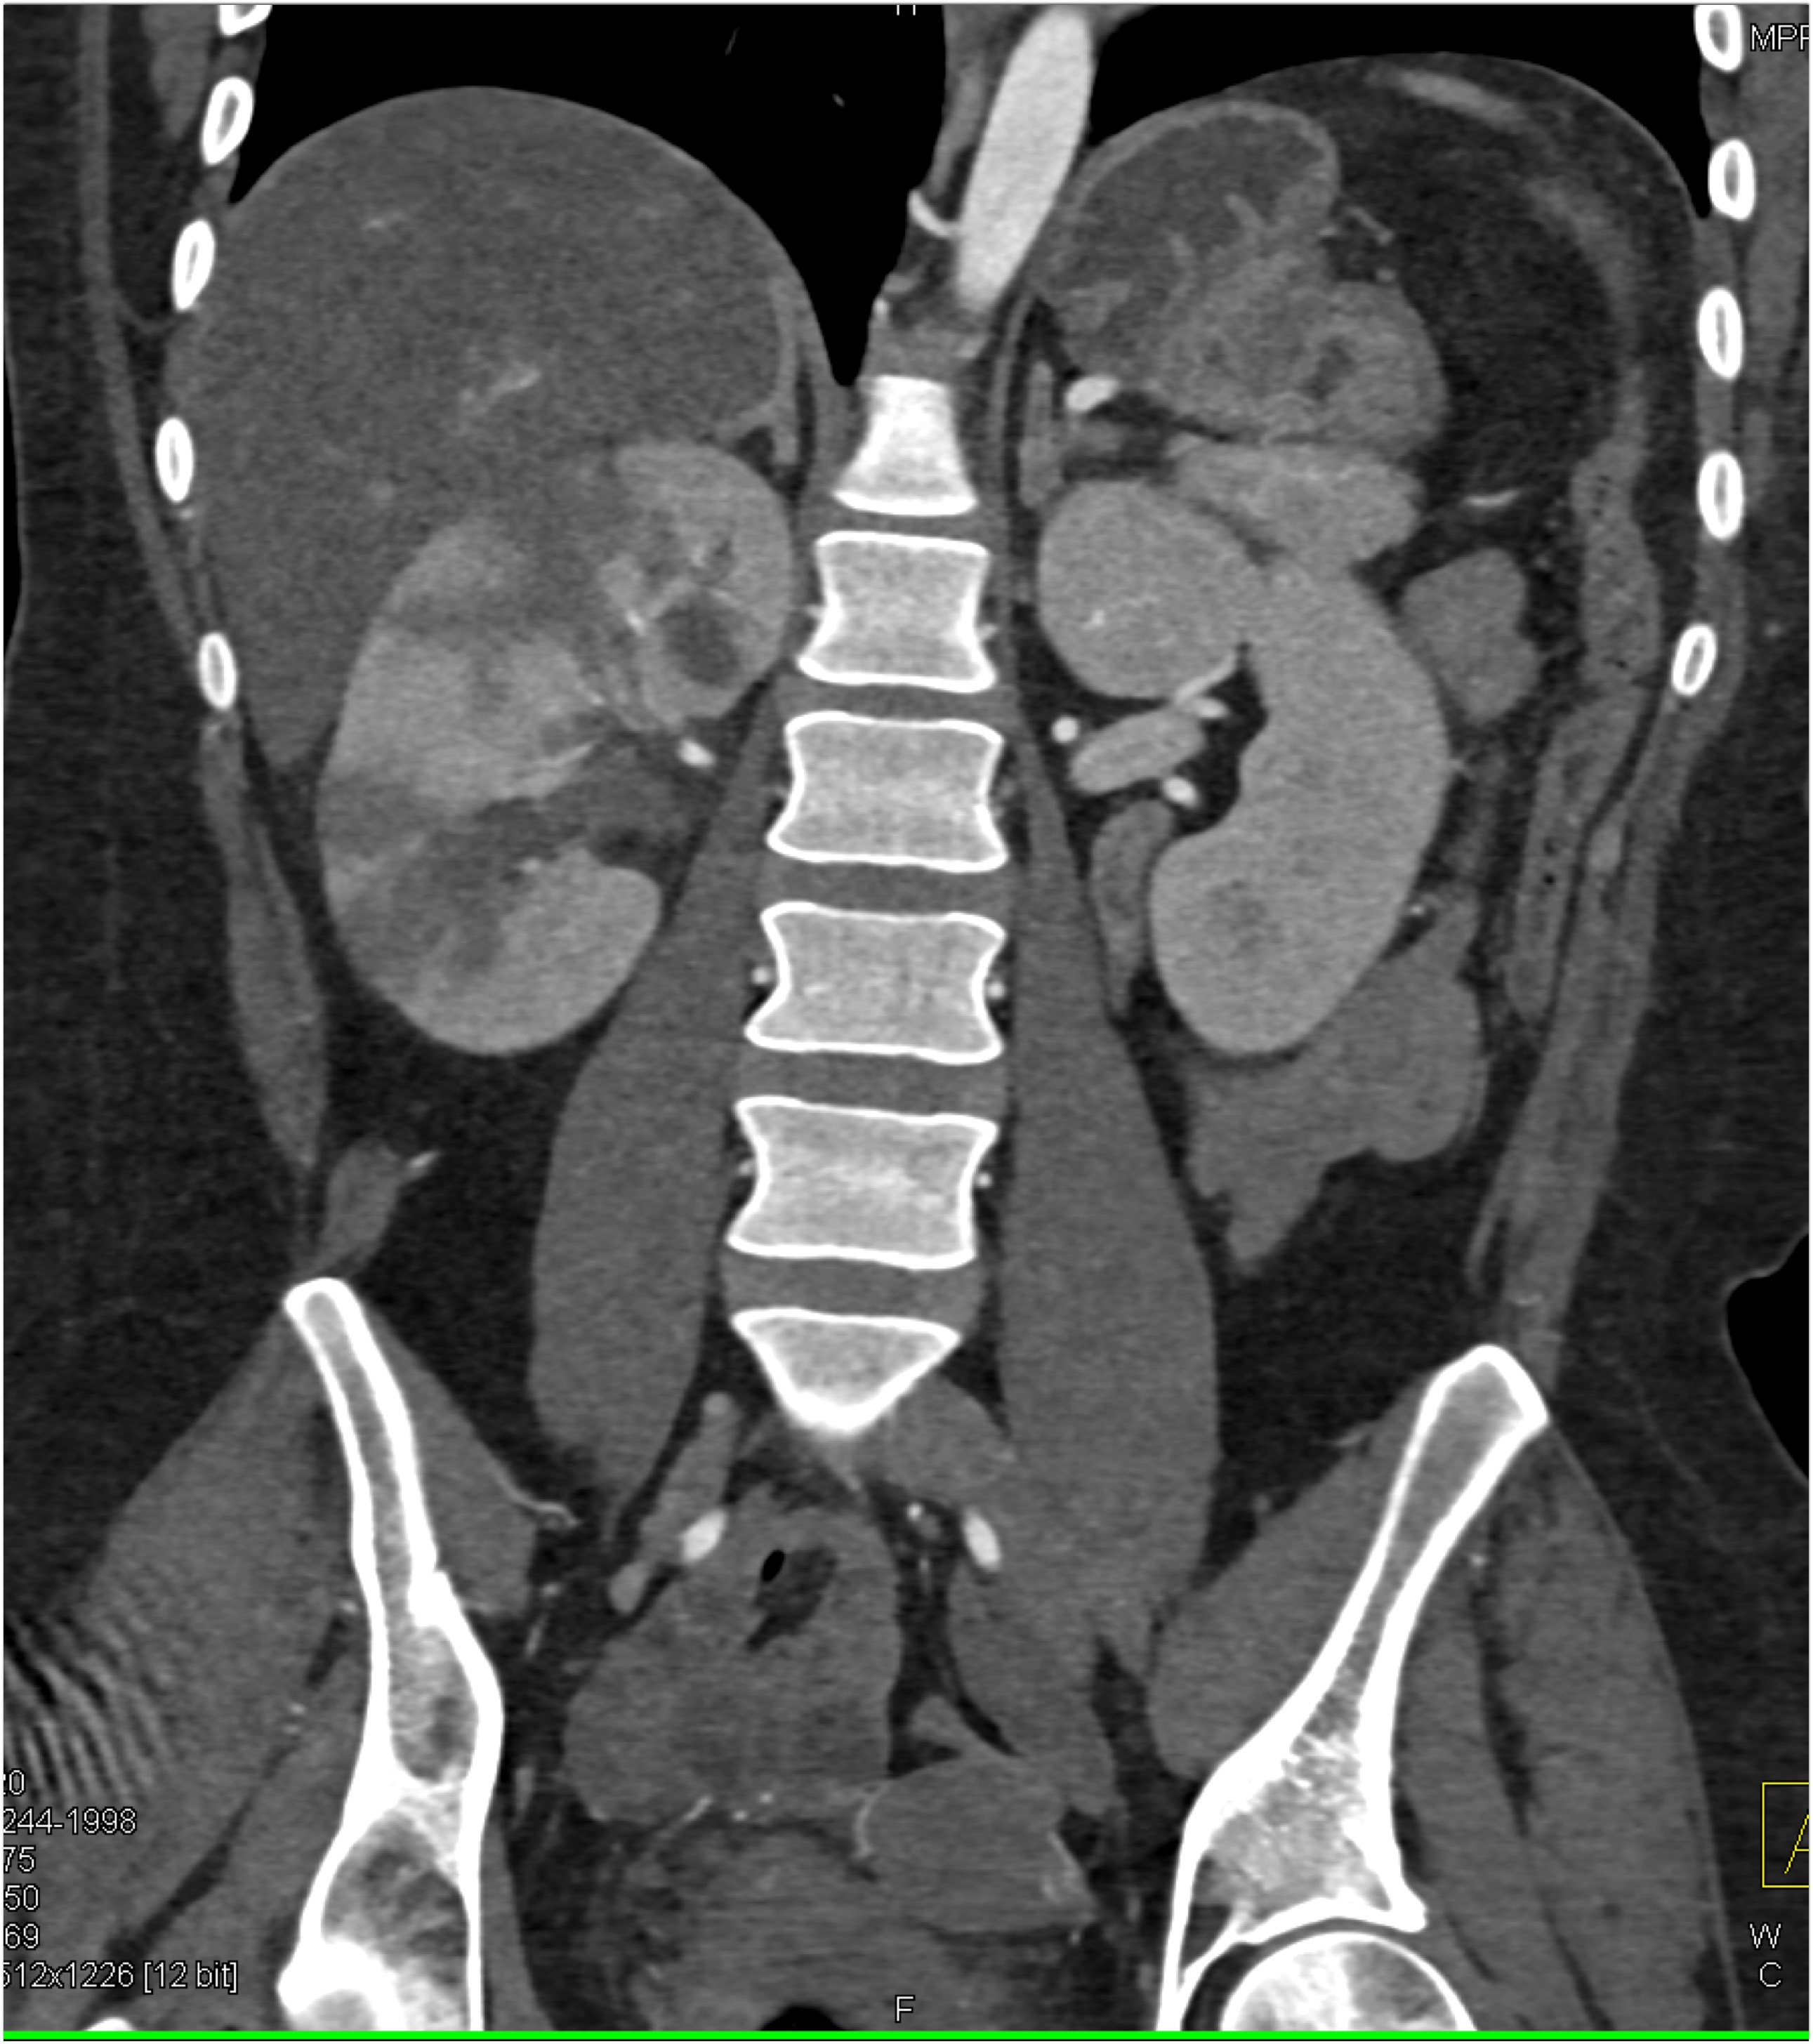

8) The most likely diagnosis for the dominant left renal mass is?

clear cell renal cell carcinoma

metastatic melanoma

papillary renal cell carcinoma

renal oncocytoma